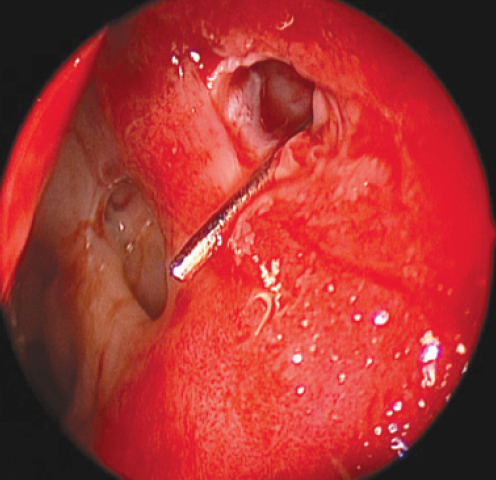

The intervention was performed as follows. Under local and conduction anesthesia with intravenous sedation, antegrade probing of the dacryostomy area was performed with the formation of an opening in the scar tissue (in three cases) and with probing of residual dacryostomy (in three cases; Fig. 2). Purulent discharge was removed from the lacrimal sac cavity using an aspirator. A balloon was inserted endonasally into the dacryostomy opening using a curved von Eicken cannula for irrigation with an outer diameter of 4.0 mm and length of 15 cm (Karl Storz, Germany; Fig. 3). Balloon dacryoplasty was performed according to the protocol we developed earlier in the experiment [8] and tested in the clinical setting (Fig. 4) [9]. The balloon was dilated at a pressure of 8 atm. for 90 s, and after 10 s, it was repeated for 60 s. After deflation, the balloon was removed. Figure 5 shows an enlarged dacryostomy after the intervention. A hemostatic sponge was inserted into the dacryostomy area, which was removed 48 h after the surgery.

Fig. 4. Endoscopic view of a left nasal cavity with an inserted and inflated balloon catheter

Рис. 4. Эндоскопическая картина полости носа (левая половина носа) с введённым и раздутым баллонным катетером